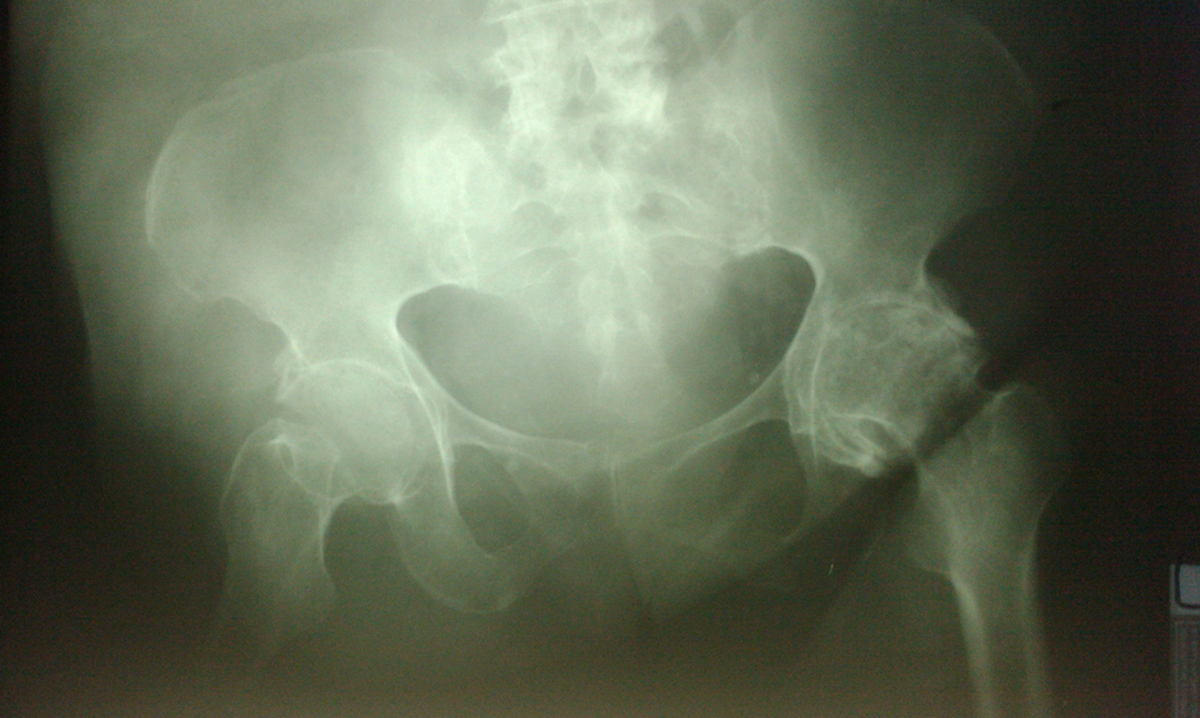

Osteoporosis is a condition wherein there is progressive bone loss, in terms of mass and density, which puts one at risk for fractures. The bone is a living matter that undergoes constant formation through deposition, and loss, through the process of resorption. These processes occur as people grow and develop, and continue onto adulthood. Bones weaken when the balance between bone formation and bone resorption is lost, such that bone density decreases, and bones become porous. This increases their risk of being broken or fractured when they are subjected even to mild stress. The bones of the spine (vertebrae), the hips and the wrist are commonly affected.

More often, however, a fracture is the first sign that one experiences before he is aware that he has osteoporosis. More than 1.5 million fractures occur annually in the US, which are related to osteoporosis. Most of these involve the spine, and the rest involve the hip, wrist, and other parts of the body.

Osteoporosis can affect anyone at any age, but elderly women are who are white or of Asian descent are more likely to be involved. However, studies show that more than two million men in the US have osteoporosis and about twelve million more are at risk of developing it. Current worldwide data shows that about one-third of all hip fractures occur in men and that more than one-third of these men die within one year after the fracture.

Weakness or thinning of the bones is often not suspected or diagnosed in men because they have a bigger bone mass than women and bone loss often occurs more slowly. However, new data from the International Osteoporosis Foundation shows that men have higher mortality rates compared to women when it comes to hip fractures. One factor that causes more serious consequences for men is that they are usually older when the fractures occur.

The best way to test bone strength and solidness is to undergo a bone mineral density test with a DEXA (dual-energy X-ray absorptiometry) scan, which is like an X-ray exam. The National Osteoporosis Foundation recommends testing men over age 70, as well as those aged 50-69 who have risk factors. Men who have noticed a height loss of more than half an inch in one year or 1 ½ inches from their original heights are also advised to take the test. Other indications for screening include men who experience back pain (since they are at risk for vertebral fracture), change in posture, and those who have a history of previous fractures after the age of 50.